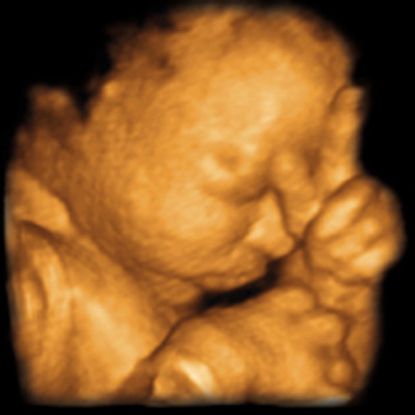

Get an early reassurance and dating scan in Manchester city centre with Lollipop 4D Baby Scans . For Β£50 you can see baby's heartbeat, check the pregnancy is developing in the correct place, obtain an estimated due date . Early scans are the only way to check whether the pregnancy is viable and are a fantastic way of obtaining peace of mind regarding . . .

Our Services . Early Dating Scan . A 2D scan from 6 weeks to confirm your pregnancy . Depending on how many weeks pregnant you are, we can work out your due date, check the number of babies and check for a heartbeat (from 6 wks) You will need a full bladder for this scan . You will receive a report and 2 thermal prints .

This early pregnancy dating scan (ante-natal scan ) is useful for those who: Are experiencing pain or bleeding in the pregnancy Had a previous miscarriages Had a previous ectopic pregnancy Are unsure of date of last menstrual period And for those who need reassurance prior to their NHS scan , now usually performed after 12 weeks .